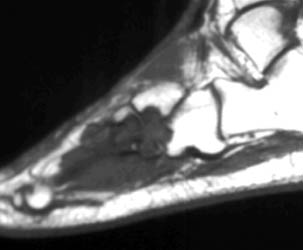

MR findings- Synovial proliferation with synovial fluid demonstrating as inhomogeneous high signal intensity on T2W images. Hemosiderine deposition is seen as low signal intensity foci on T1W and T2W images. Cystic bony erosions are present in fifty percent of patients.

26 years old female presenting with painful soft tissue mass at the plantar aspect of the left foot.MR demonstrates this mass is isointense on T1,isointense to minimally hyperintense on proton density and hyperintense on T2 W and Stir images. Bony erosions are identified in 3rd cuneiform, cuboid and bases of 3rd and 4th metatarsals on MRI and plain radiographs.Few foci of low signal intensity hemosiderine deposits are identified on all pulse sequences.